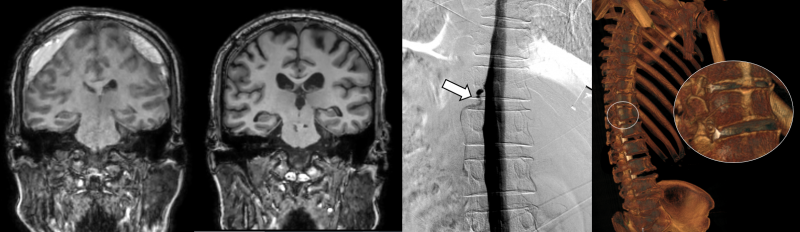

일반적인 자발성 두개내 저압증과는 달리 아형인 뇌척수액 정맥 누공은 MRI에서는 정상 소견을 보일 수 있어 원인 규명부터 치료까지 난항을 겪는 질환이다.

실제로 이번에 치료를 받은 뇌척수액 정맥 누공이 있던 환자 4명 모두는 세브란스병원에 오기 전 뇌압이 낮아져 두통이 생기는 ‘자발성 두개내 저하증’이 의심됐으나, 척추 MRI와 단순 척수 조영술 검사에서는 전부 정상 소견을 보였다.

세브란스병원은 최근 DSM을 국내 최초로 도입해 이 같은 기존 진단법의 한계를 극복했다.

DSM(Digital Subtraction Myelography, 디지털 감산 척수조영술)은 척수에 조영제를 주입하고 모니터 화면으로 뇌척수액의 흐름을 실시간으로 확인할 수 있다. 이를 통해 뇌척수액이 새나가는 구멍을 정확하게 찾아낼 수 있게 됐다.

DSM과 더불어 세브란스병원이 함께 진행 중인 측위 CT 척수 조영술까지, 모두 뇌척수액 정맥 누공을 진단할 수 있는 최신 기법이다.

이번에 세브란스병원을 찾은 환자들은 DSM 검사와 측위 CT 척수 조영술로 뇌척수가 새어나가는 부위를 정확히 진단, 치료받고 뇌압을 회복했으며 경막하출혈도 사라졌다. 이에 환자들에서 보였던 인지기능 저하와 보행장애가 모두 호전됐다.